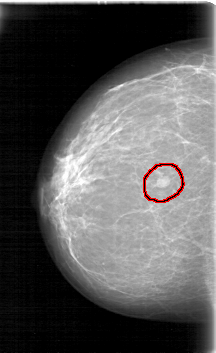

FILE: D_4090_1.RIGHT_CC.OVERLAY

TOTAL_ABNORMALITIES 1

ABNORMALITY 1

LESION_TYPE MASS SHAPE OVAL MARGINS ILL_DEFINED

ASSESSMENT 0

SUBTLETY 5

PATHOLOGY BENIGN

TOTAL_OUTLINES 1

BOUNDARY

RIGHT_CC LINES 5281 PIXELS_PER_LINE 3226 BITS_PER_PIXEL 12 RESOLUTION 43.5 OVERLAY